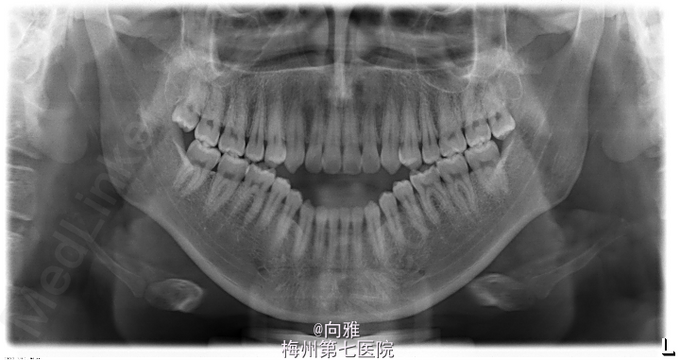

青年男患者,下颌前突十余年,患者于十年余前无明显诱因出现上颌后缩,下颌前突,影响美观及咬合,逐渐加重,未行处理,1年前于我院正畸科就诊,制定“正畸-正颌联合”治疗方案,遂行正畸治疗,现已完善术前正畸,今为行正颌手术入院治疗

双侧颌面部基本对称,侧面观:面下1/3前突。左侧颞下颌关节触及弹响,右侧颞下颌关节未触及弹响,双侧颞下颌关节无压痛。开口型“↓”,开口度3.5cm。口内全口牙列正畸托槽,前牙开合、反合,约2cm,双侧后牙I类关系。

1.下颌前突 2.偏颌畸形,全麻下行BSSRO后退术+双侧下颌骨去骨皮质术+坚固内固定术